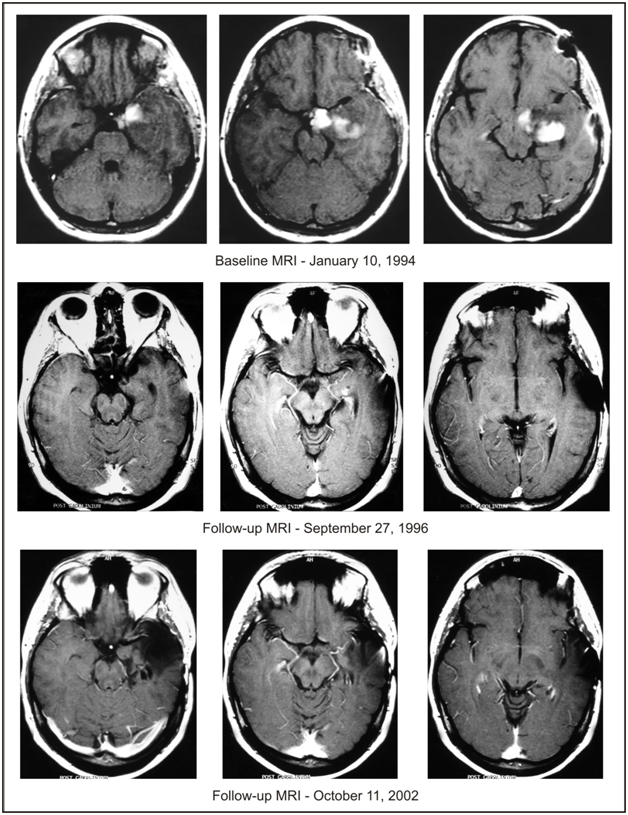

Follow-up brain MRIs at 3 and 14 months from treatment start did not show significant changes. However, all of the patient’s symptoms except epileptic seizures disappeared by 13 months. Head MRIs at 23 and 29 months of treatment showed the corresponding two largest perpendicular diameters of the contrast enhancing lesion to be approximately 1.3x0.3 cm and 1.0x0.2 cm, respectively, indicating a 96% and 98% decrease, respectively, compared to the MRI at the time of the patient’s presentation to our clinic. Further, follow-up MRI at 32 months after presentation to our clinic showed complete disappearance of the enhancing lesion, versus questionable minimal enhancement indicating the beginning of a CR. At this point, the patient’s mild seizures occurred approximately once per month, were associated with her menstrual cycle, and were suspected to be triggered by a scarred area of brain which was residual to the CR.

Based on a similar follow-up MRI at 37 months after presentation, treatment with intravenous ANP was discontinued at 40 months, and the patient continued maintenance treatment with ANP A10 and AS2-1 capsules at a dosage of 0.14 g/kg/day each. Follow-up MRIs at 45, 51 and 55 months after presentation to our clinic confirmed CR and antineoplaston treatment was discontinued at 56 months. At 58 months, the patient underwent resection of gliosis scar causing seizures. Pathologic evaluation of the biopsy did not demonstrate any presence of astrocytoma, and the concluding diagnosis was mild grade cerebral cortical dysplasia representing a glioneuronal hamartoma. The patient recovered well from surgery and has not had any epileptic seizures since then. The details of her diagnosis and treatment are shown in Table 1. Follow-up MRIs, shown in Figure 1, between 6 and 15 years after presentation to our clinic have not shown any tumor recurrence. Importantly, the patient did not report any serious adverse events due to antineoplastons.

Figure 1 Baseline MRI of the head with contrast. Follow-up MRI of the head with contrast on September 27, 1996, indicating complete response. Follow-up MRI of the head with contrast on October 11, 2002, after resection of gliosis scar, indicating continuation of complete response.